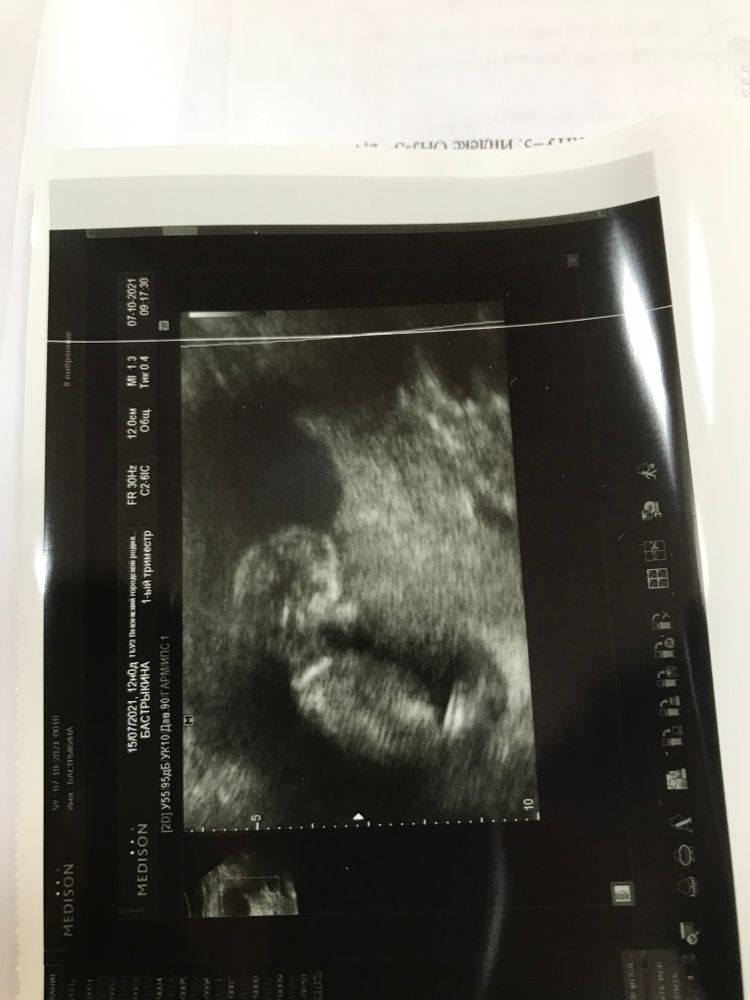

12 н Узи. Давайте погадаем пол.

Поздравляю, что все хорошо! А пол не понятно, не видно бугорка

Думаю мальчик. Но это так - по внешнему виду, бугорка не видно

Анастасия, почему то тоже профиль показался мальчишичьим)

Поздравляю с отличным скринингом 🤗! На счёт пола,не скажу,не разбираюсь совсем 🙈

Настасья, но пол конечно не главное! Главное что что все соответствует сроку и все в норме! Важнее этого нет нечего!